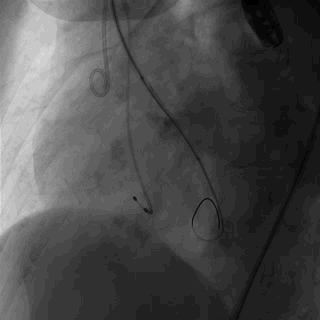

· 血管入路:右侧股动脉,逐步扩张后置入大鞘,左侧颈动脉备用。

手术过程

使用18Fr内芯预扩右侧股动脉,再使用19Fr内芯预扩,最后置入19Fr鞘管。同时左侧颈动脉备用,以便一旦股动脉途径入路失败,可以迅速更改为颈动脉途径。

4.患者股动脉尺寸偏小为临界值,一旦输送鞘不能顺利通过股动脉,则需要有备用方案如选择经颈动脉途径。

3. 该病例患者股动脉尺寸为临界值,诸如股动脉尺寸偏小,一旦输送鞘不能顺利通过股动脉,则需要选择经颈动脉途径。针对该特点手术团队使用18Fr内芯预扩股动脉,再使用19Fr内芯预扩,最后顺利置入19Fr鞘管。同时左侧颈动脉备用,以便一旦股动脉途径入路失败,可以迅速更改为颈动脉途径。